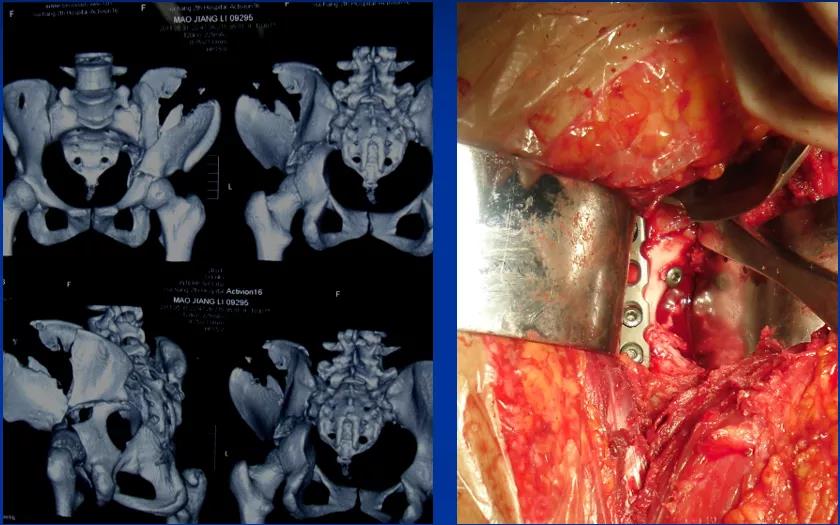

——典型案例——

微创插板病历后路有限切开,结合前路微创插板内